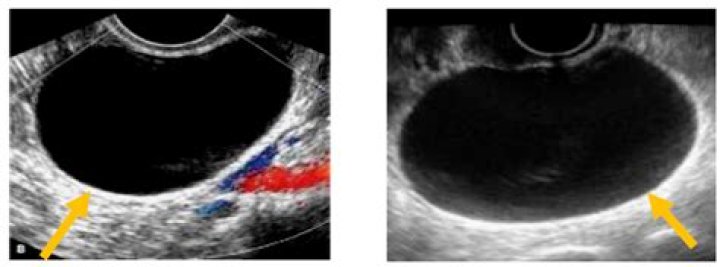

Ovarian cysts can sometimes be detected during a pelvic examination, although an imaging test, usually a pelvic ultrasound, is necessary to confirm the diagnosis. Computed tomography (CT) scan or magnetic resonance imaging (MRI) are also sometimes used, but less commonly.